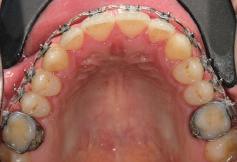

20 Dental Tribune Bulgarian Edition / октомври 2022 г. П ациентите със завършен растеж и скелетни проблеми обикновено представляват предизвикателство за ортодонт ската практика. Необходимостта от изваждане на зъби в комбинация с особеностите на възрастовата ортодонтия изисква особено внима ние. Фокусът върху критично важното значение на позицията на долните резци във връзка с дългосроч ната стабилност и постигането на оптимални оклузални взаимоотношения при затварянето на екстракционните пространства лесно може да излезе извън контрол. Когато към тези чисто кли нични проблеми се добави и стресът от натоваре ната практика, предизвикателството става още по-голямо. Всички тези фактори налагат използ ването на доказан подход с ясни и последовател ни стъпки, в което се разкрива силата на дисциплината „Алекзандър“ – предвидим протокол през целия процес на елиминиране на ротациите, ниве лиране на дъгите, затваряне на екстракционните пространства и финализиране на случая. Именно такъв е и случаят, който презентираме –екстракционен, скелетен клас 3 при възрастен па циент, лекуван по системата „Алекзандър“. ПРЕДВИДИМИ РЕЗУЛТАТИ ПРИ ПАЦИЕНТИ СЪС ЗАВЪРШЕН РАСТЕЖ И СКЕЛЕТЕН КЛАС 3, ИЗПОЛЗВАЙКИ ЕКСТРАКЦИОННО ЛЕЧЕНИЕ ПО ДИСЦИПЛИНАТА „АЛЕКЗАНДЪР“ Д-р Радой Димитров, България Преди започване на лечение клиничен случай | ортодонтия Фиг. 1а–1e Преди започване на лечение. Пациентът пристига в практиката с основното оплакване от невъзмож ност за нормално дъвчене. Снета е цялата необходима диагностична ин формация. Фиг. 1f–1h Снимки в профил и анфас. Фиг. 1i–1k Панорамна снимка, телерентгенография и анализ на телерент генография. Фиг. 1а Фиг. 1d Фиг. 1f Фиг. 1g Фиг. 1h Фиг. 1e Фиг. 1b Фиг. 1c Фиг. 1i Фиг. 1j Фиг. 1k

closed.

21Dental Tribune Bulgarian Edition / октомври 2022 г. ДИАГНОСТИЧНИ РЕЗУЛТАТИ: 1. Възраст на пациента: 21 години 2. Скелетен клас III (ANB 0) 3. Зъбен клас 3 4. Ръбцова захапка във фронта, кръстосана в дисталните участъци 5. Тясна горна челюст 6. Overjet – 0 мм, Overbite – 0 мм 7. Несъответствие на горната с долната средна линия 8. Единични контакти в ЦО 9. Хиподивергентен тип на растеж SN/MP – 33.5 10. Неравен гингивален контур 11. Неравна линия на усмивката 12. Тенденция за рецесии в долен фронт ПРЕПОРЪЧИТЕЛНО ЛЕЧЕНИЕ: Пълно ортодонтско лечение с метални брекети „Алекзандър“ Корекция на клас 3 захапката в областта на кучешките зъби с екстракция на първите пре молари в долна челюст Корекция на кръстосаната захапка в дистални участъци Коригиране на ръбцовата захапка във фронта Подобряване на ОJ и OB на пациента Стрипинг в долен фронт Подреждане на зъбите в горната и долната челюст Професионално хигиенизиране и профилактични дентални прегледи са препоръчителни на всеки 6 месеца. 1-ви месец След 1 месец са залепени брекети в горната челюст – поставена е еластична дъга. 016 NiTi. В долната челюст са елиминирани ротациите, поставена е стоманена дъга. 016SS, закалена с ток, и еластична верижка за затваряне на пространствата. 3-ти месец В долната челюст е поставена трета дъга – 17 x 25 NiTi с къси лигатури и верижка

В горната челюст се затварят пространствата с дъга .016SS и верижка. 5-и месец На 5-ия месец след залепяне на брекетите в долната челюст е поставена стоманена дъга 16 x 22 SS с четвъртито сечение, омега луп и тай бек. В горната челюст е поставена дъга 17 x 25 NiTi. Поради липсата на стабилни оклузални контакти са поставени лингвални верижки в областта на моларите, за да се предотврати нежелана ротация на 7-ите зъби. 6-и месец На 6-ия месец от началото на лечението са екстрахирани долните първи премолари, поставена е дъга 16 x 22 SS със затваряща чупка teardrop. Чупката се активира всеки месец по 1 мм с чинч-бек. клиничен случай | ортодонтия СТЪПКИ НА ЛЕЧЕНИЕТО Начало на лечението Лечението започва с поставяне на апарат за бърза експанзия в горната челюст. През първия месец от лечението са направени 24 оборота на апарата за експанзия. Залепени са брекети в долната челюст, поставена е дъга 17x25 CuNiTi, като са предпи сани клас 3 ластици (1/4”,4 1/2 oz) по време на сън, за да се осигури контрол върху торка на долните резци. Фиг. 2а Фиг. 3a Фиг. 4a Фиг. 3b Фиг. 4b Фиг. 3c Фиг. 4c Фиг. 3d Фиг. 4d Фиг. 3e Фиг. 4e Фиг. 5a Фиг. 5b Фиг. 5c Фиг. 5d Фиг. 5e Фиг. 6a Фиг. 6b Фиг. 6c Фиг. 6d Фиг. 6e Фиг. 7a Фиг. 7b Фиг. 7c Фиг. 7d Фиг. 7e Фиг. 2b Фиг. 2c Фиг. 2d

Dental Tribune Bulgarian Edition / октомври 2022 г.22 клиничен случай | ортодонтия 14-и месец В горната и долната челюст са поставени последни стоманени дъга с омега луп и тай бек – 17 x 25 SS с четвъртито сечение. Назначени е ластик за средната линия в комбинация с клас 3 ластик (1/4”, 6 1/2 oz). Контролни рентгенографии 13-и месец Екстракционните пространства са затворени. Направена е контролна панорамна снимка за оценка позицията на корените. Взето е решение за презалепване на брекетите на 12, 22 и пръстените на 36 и 46. 21-ви месец Средната линия в горната и долната челюст съвпадат. Ластиците са спрени. Свалени са пръстените и брекетите в горната и долната челюст, зигзаг ластици не са използвани поради благоприятните оклузални взаимоотношения. Фиг. 11j Ортопантомография в края на лечението. Фиг. 11k Телерентгенография след края на лечението. Фиг. 11l Анализ на телерентгенографията след лечението. Фиг. 11m Последователност на дъгите в горната и долната челюст Фиг. 11n Суперимпозиция на PreOp и PostOp ортопантомографии. 10-и месец Затварянето на пространствата е предвидимо и контролирано, без да се отварят пространства в зъбната дъга. Фиг. 8a Фиг. 8b Фиг. 8c Фиг. 8d Фиг. 8e Фиг. 10a Фиг. 10b Фиг. 10c Фиг. 10d Фиг. 10e Фиг. 9a Фиг. 9b Фиг. 9c Фиг. 9d Фиг. 9e Фиг. 9f Фиг. 11a Фиг. 11f Фиг. 11j Фиг. 11l Фиг. 11m Фиг. 11n Фиг. 11k Фиг. 11g Фиг. 11h Фиг. 11i Фиг. 11b Фиг. 11c Фиг. 11d Фиг. 11e

Dental Tribune Bulgarian Edition / октомври 2022 г. 23клиничен случай | ортодонтия реклама Лечението е продължило 21 месеца. Проведено е домашно избелване с индивидуални шини. За автора: Д-р Радой Димитров завършва с отличие Факултета по дентална медицина към МУ–София през 2015 г. В продължение на 5 години работи в няколко водещи практики в София, като през 2019 г. заедно със своята съпру га д-р Траяна Димитрова основават собствена практика в гр. Гоце Делчев –Dimitrovi Dental Care. Посещава редица курсове за повишаване на квалификаци ята, но най-сериозен тласък в развитието на ортодонтската си практика получава след завършването на комплексната ортодонтска програма, воде на от д-р Иван Горялов, базирана на дисциплината „Алекзандър“ – система с повече от 50 години опит в целия свят. Д-р Димитров е член на Българския изследователски клуб „Алекзандър“. Взе ма участие като гост-лектор в симпозиума с международно участие The Power of the Alexander Discipline, който се проведе на 14–15.05.2022 г. С д-р Ди митров можете да свържете на тел. +359885 252 025. Заключение Представеният случай е ярък пример за възможностите и красо тата на дисциплината „Алекзандър“ – приложен е утвърден под ход с ясни правила и са постигнати очакваните цели. Резулта тът ще бъде дългосрочно стабилен, тъй като са спазени всички правила, които се отнасят към максимално комфортната пози ция на зъбите в края на лечението. Постигнати са красива усмив ка и стабилна оклузия. ПОСТИГНАТИ РЕЗУЛТАТИ ОТ ЛЕЧЕНИЕТО 1. Коригирана ръбцова захапка 2. Коригирана клас 3 захапка в областта на ку чешките зъби 3. Коригирана кръстосана захапка в дисталните участъци 4. Коригиран овърджет и овърбайт 5. Разширена е горната зъбна дъга 6. Подредени зъби в горната и долната челюст 7. Постигната е стабилна захапка с множество контакти в ЦО 8. Драматично е подобрена дъвкателната функ ция 9. Подобрена е линията на усмивката ДРУГИ ПРОВЕДЕНИ ДЕНТАЛНИ ПРОЦЕДУРИ 1. Домашно избелване на зъбите 2. Екстракция на мъдреците Фиг. 12a Фиг. 12b Фиг. 12c Фиг. 12eФиг. 12d Фиг. 12f Фиг. 12g Информация за дати, цени и отстъпки www.bracescourses.com 0889 22 55 01 Практически курсове лектор д-р Иван Горялов Дисциплината „Алекзандър“ ПЪТЯТ КЪМ СУПЕРУСМИВКИТЕ 100% връщане на цялата сума, ако не сте удовлетворени след преминаване на Ниво 1 Директно и индиректно залепяне на брекети Анализ, диагноза и план на лечение Лечение на клас 2 дълбока захапка Екстракционно лечение Лечение на клас 3 отворена захапка НИВО 5НИВО 1 НИВО 2 НИВО 3 НИВО 4